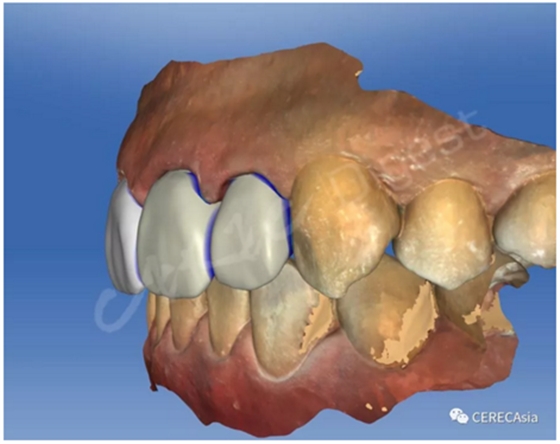

因?yàn)楸緛砭褪莻溲肋^的牙齒,拆掉就牙套后較難確認(rèn)需重新備牙的量,尤其舌側(cè)及頰側(cè)的齒頸部等處最容易發(fā)生厚度不足的狀況,因此我反覆檢查 舌側(cè)的間隙 (如左圖),口內(nèi)看似足夠但看看右圖就會(huì)發(fā)現(xiàn)空間仍然不足。右圖的藍(lán)色半透明區(qū)域?yàn)樽钚『穸?,就是從支臺(tái)齒往外再加上各個(gè)區(qū)域分別設(shè)定的最小厚度得到的結(jié)果,可以看到些微穿過下排的牙齒。

圖四、軟件中有很多方法可以確認(rèn)空間是否足夠,其中一種方法就是看最小厚度離對(duì)咬牙的距離,右圖可見最小厚度已穿越對(duì)咬牙,代表空間不足。